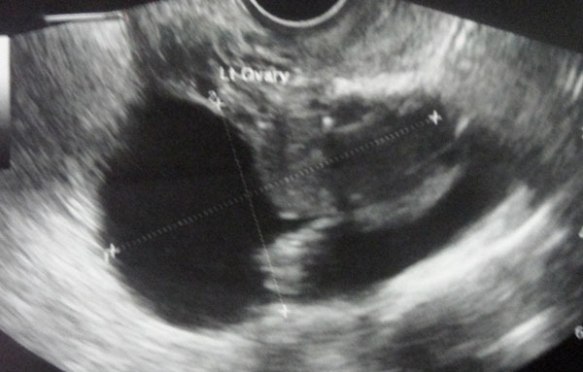

CT scan done on 18 January 2013 indicated a large uterus. There is a large posterior wall uterine myoma measuring 6.6 x 8.4 x 8.9 cm with central hypodensity likely to represent necrosis. It causes anterior displacement of endometrial and bladder depression.

Bilateral ovarian cysts. Right ovarian cyst measures 3.2 x 3.7 cm and left ovarian cyst measures 2.8 x 5.2 cm. There is an suggestion of left hydrosalphinx.

E-53--a

E-53--b